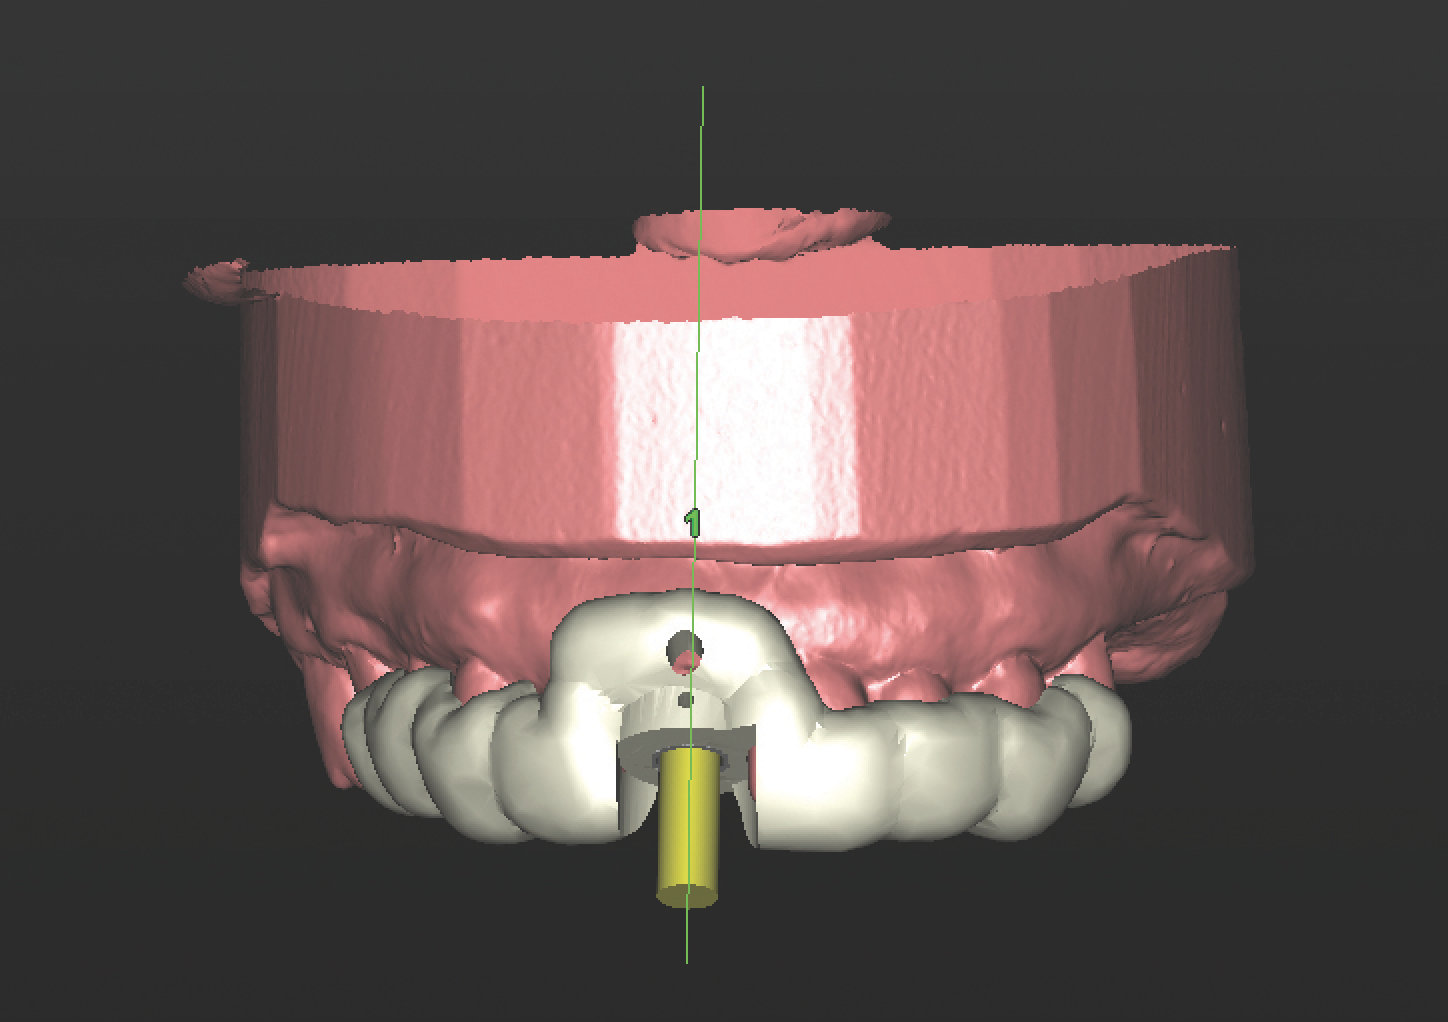

With all of this needed information relative to the pre-operative condition and proposed final tooth position, the treatment moved into the assessment and planning phase. The CBCT revealed an intact buccal plate anterior to the root of tooth No. 8 with adequate bone surrounding the area in all dimensions. Because of the favorable bony contours, an immediately placed implant was decided upon and planned in the software. The CEJ of the proposed final tooth location was identified and an OsseoSpeed EV 4.2 C - 11 mm implant (Dentsply Implants) was planned 3 mm apical and 2 mm lingual to that landmark12 to assure adequate biologic and prosthetic space for the final restoration (Figure 3 through Figure 5). A Simplant SAFE Guide was selected and ordered to convey all of the positional parameters of the final implant position, including depth control and implant timing.

The prosthetic components of the case also were planned at this time. The Simplant file registering all of the positional attributes of the implant was then imported into the Atlantis Abutment software by selecting the Immediate Smile protocol option. This allows a final abutment to be designed from the proposed implant plan. A fully anatomic patient-specific abutment in gold-shaded titanium was selected to achieve optimal soft tissue and prosthetic support.13 The digital file representing the abutment was then exported via an Atlantis Core File and imported into the 3Shape software to design an acrylic resin interim prosthesis. The surgical guide, patient-specific abutment, and interim prosthesis crown were all manufactured and returned prior to the surgical date (Figure 6).